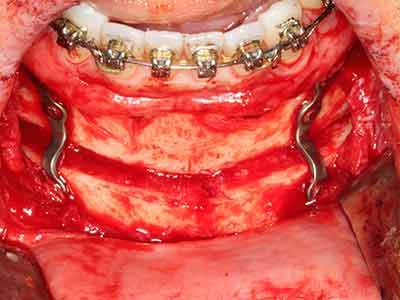

Fig. 18: Preparación de una tapa cortical con la sierra ósea piezoeléctrica (Piezomed, W&H).

Fig. 19: Zona operada después de neurolisis y eliminación del osteomo.

Fig. 20: La tapa ósea extraída se readapta y se fija mediante un tornillo para osteosíntesis (KLS Martin, Tuttlingen).